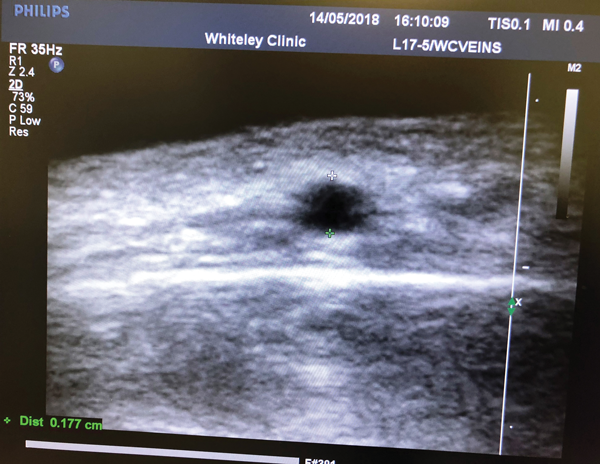

Figure 7: Ultrasound of forehead vein in transverse section.

The scale shows that the vein is 0.177 cm in diameter and is about the same depth.